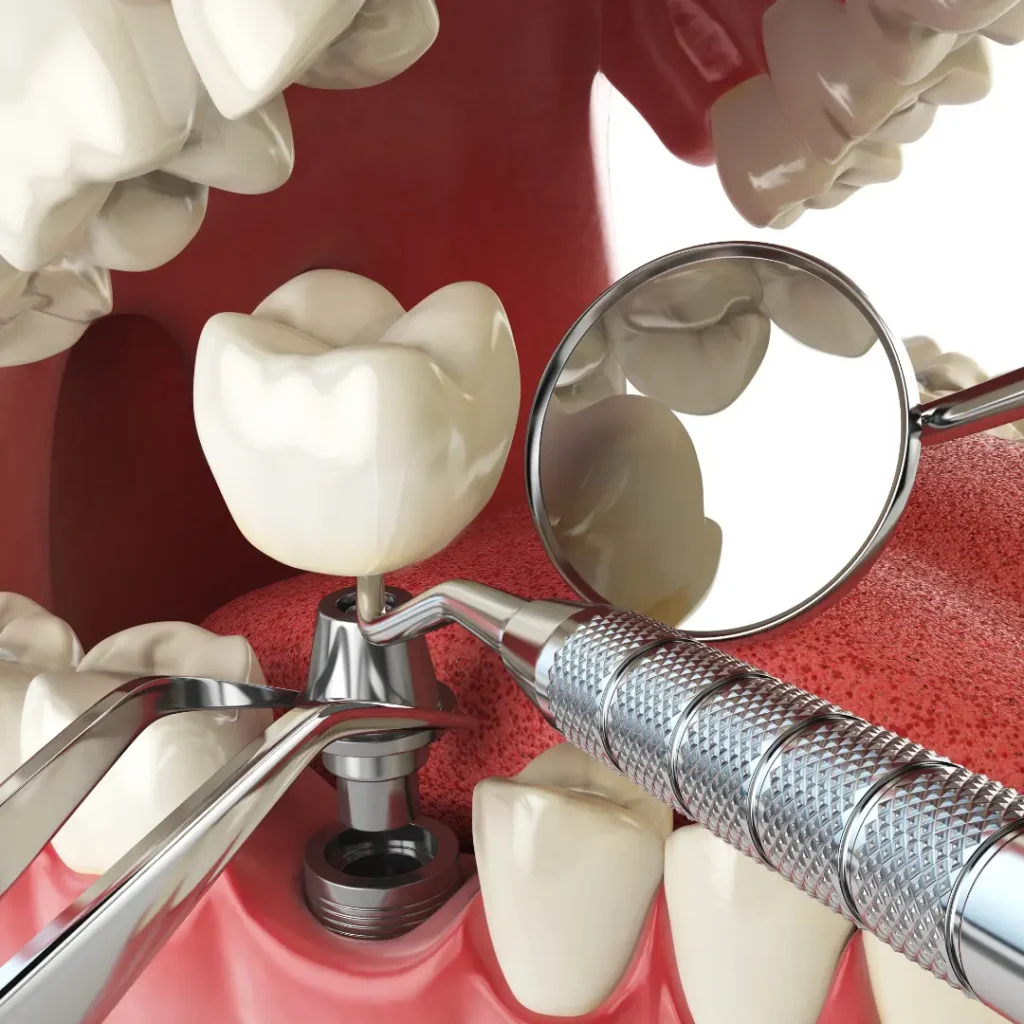

Emergency Dental Implant Services We Offer:

• Same-Day Emergency Dental Implants

• Implant Repairs & Replacements

• Loose or Broken Implant Treatment

• Emergency Extraction + Immediate Implant Options

Common Dental Implant Emergencies We Treat

Cracked or fractured implants

Loose or shifting dental implants

The implant crown fell off or broke

Infection or pain around an implant

Trauma-related tooth loss needs immediate implants